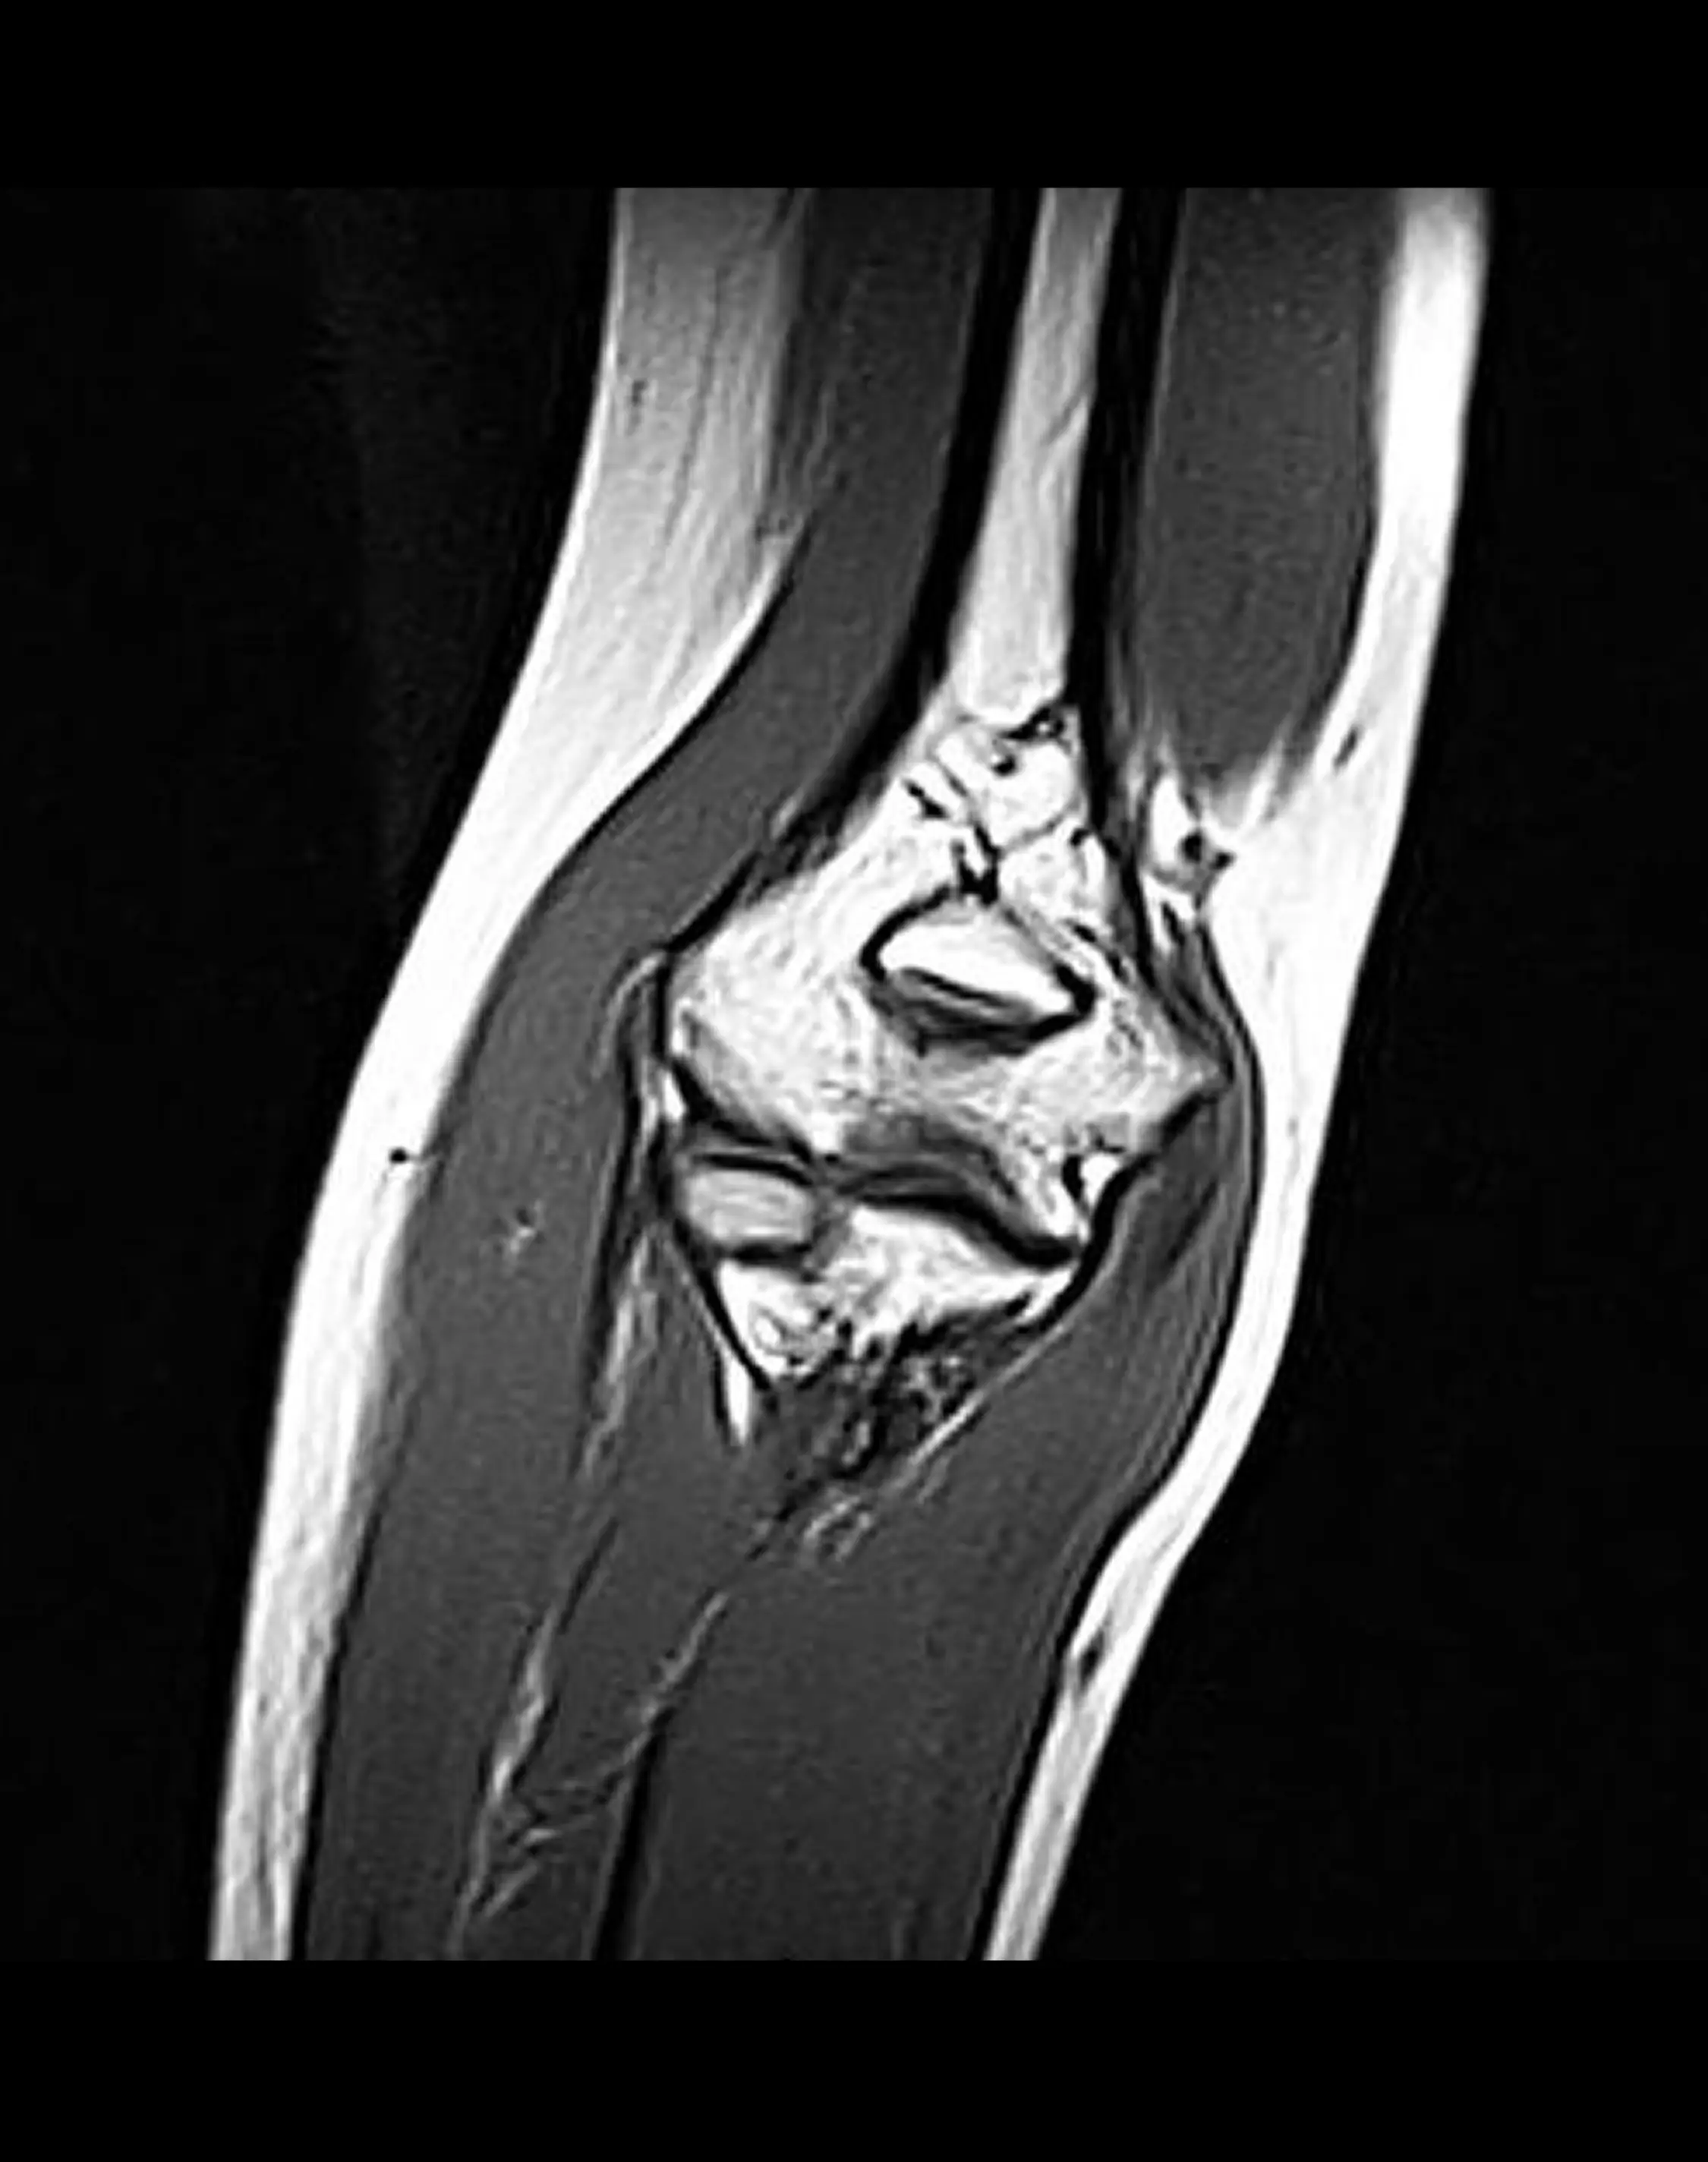

МРТ локтевого сустава

МРТ локтевого сустава — диагностическая процедура, позволяющая детально оценить состояние костей, хрящей, связок, сухожилий и мягких тканей локтевого сустава, выявить травмы, воспаления и дегенеративные изменения.